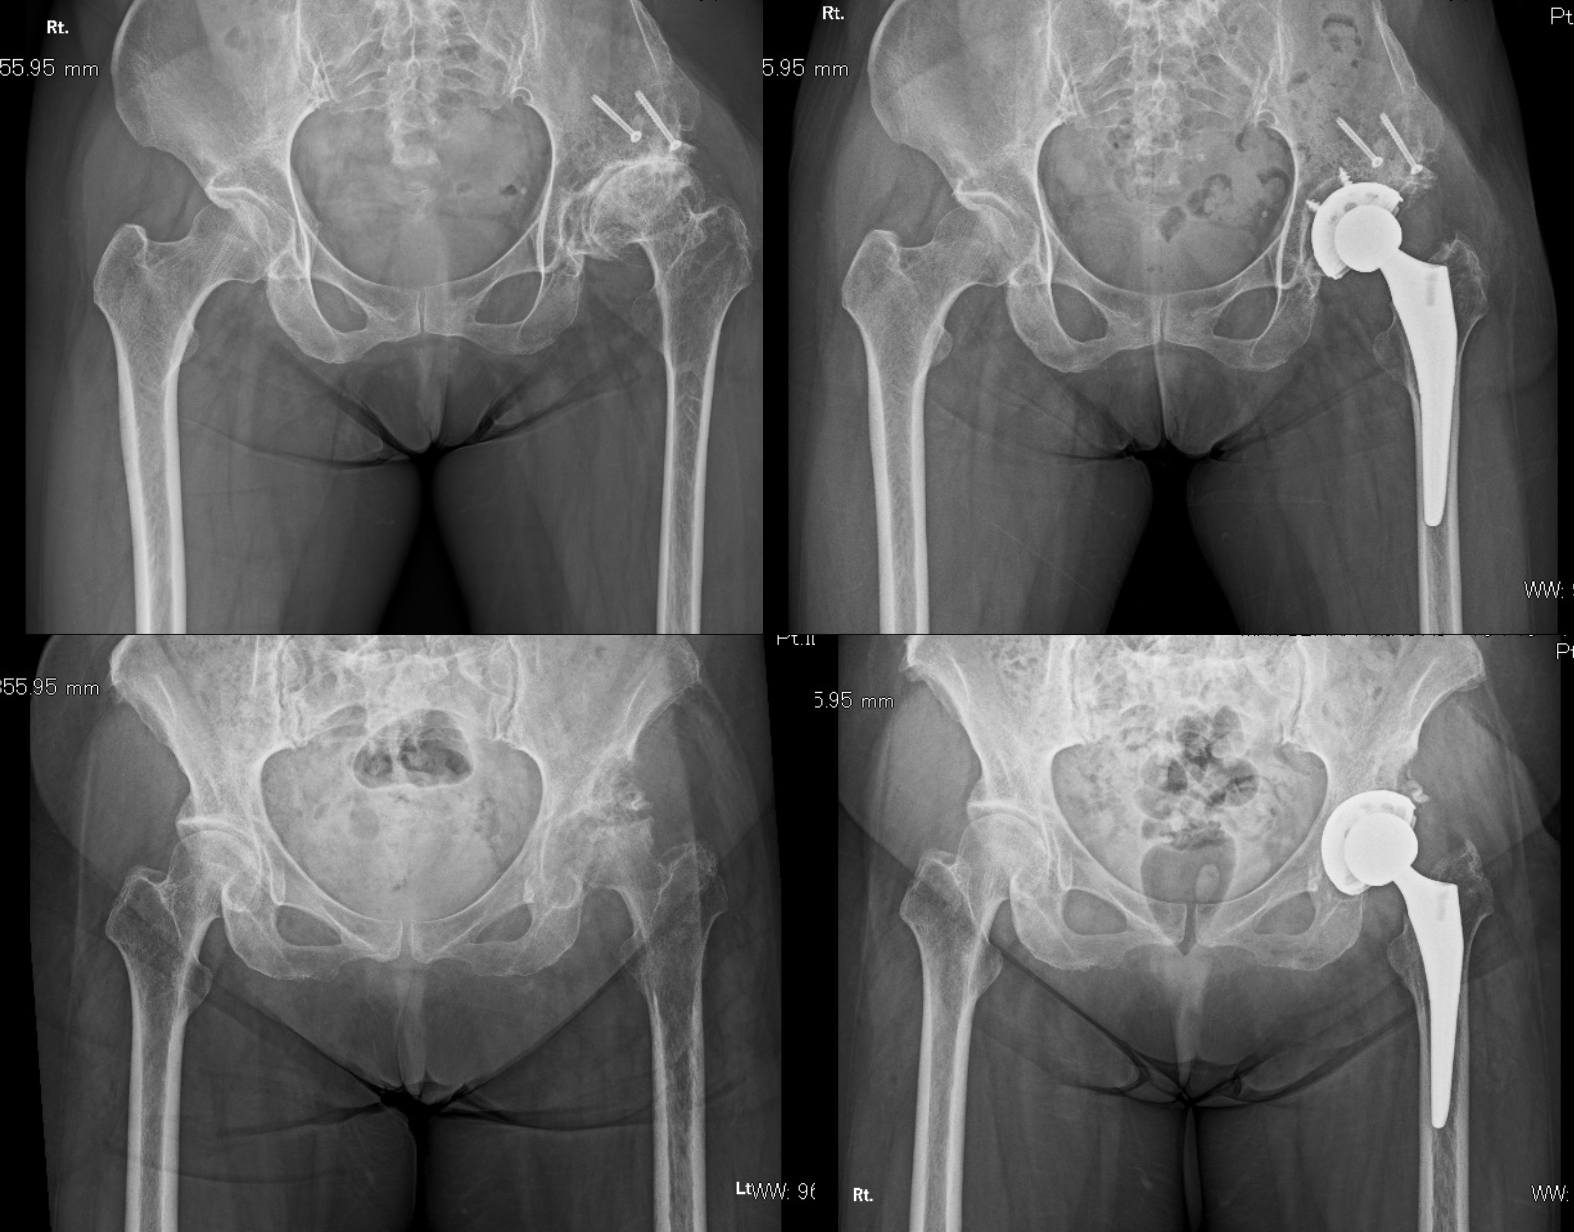

人工股関節置換術(骨頭置換術)

人工股関節置換術(Total hip arthroplasty、THA)では、術前のCT画像を基にコンピューターを用いた3次元術前計画を行います。その計画を詳細に検討し、ナビゲーションシステムを使用してSuperiorアプローチと呼ばれる従来の後方アプローチから派生したMIS(最小侵襲手術)を行っています(SuperPathもしくはDirect superior approach)。そのため術後の動作制限・禁忌肢位等は基本的に設けておらず、しゃがみこみ(squatting)、足を組むといった動作をゴールとしています。

また画像にあるようなシビアな症例でもしっかりと解剖学的・生理的に好ましい人工関節を設置することが可能です。